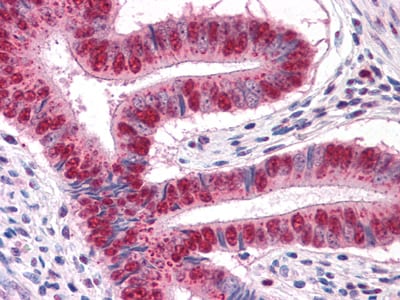

分类: 科研抗体货号: 30084别名: HKI; HXK1; HK1-ta; HK1-tb; HK1-tc; HK1应用: WB,IHC,IF反应种属: Human,Mouse,Rat